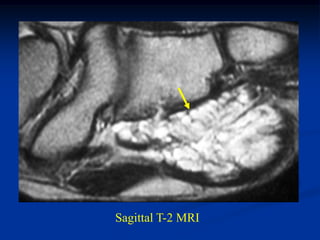

Case #1197

CLASSIC

37 year female with

hibernoma triceps m

Axial T-2 MRI